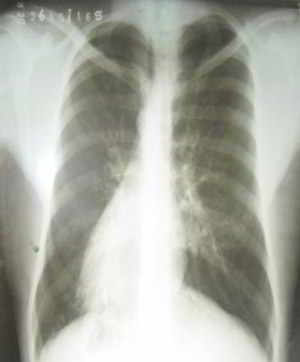

Figura 2

Ecocardiograma: Dextrocardia mas situs inversus, corazón y grandes vasos de estructura y función normal.

Ultrasonido Abdominal: Hígado en Hipocondrio Izquierdo, bazo y cámara gástrica situado en hipocondrio derecho.